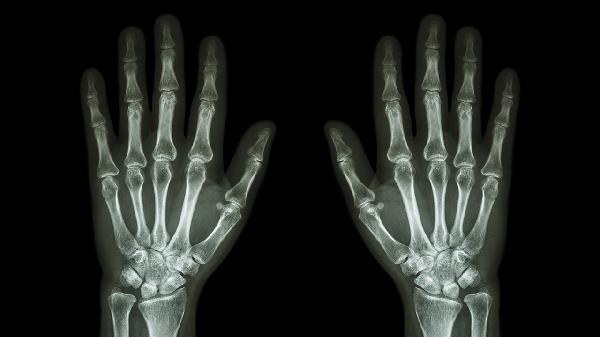

右手中指关节处长个硬疙瘩怎么回事

右手中指关节处长硬疙瘩可能与腱鞘囊肿、骨关节炎、类风湿结节、痛风石、表皮样囊肿等因素有关,可通过局部热敷、药物治疗、手术切除等方式处理。建议及时就医明确诊断。